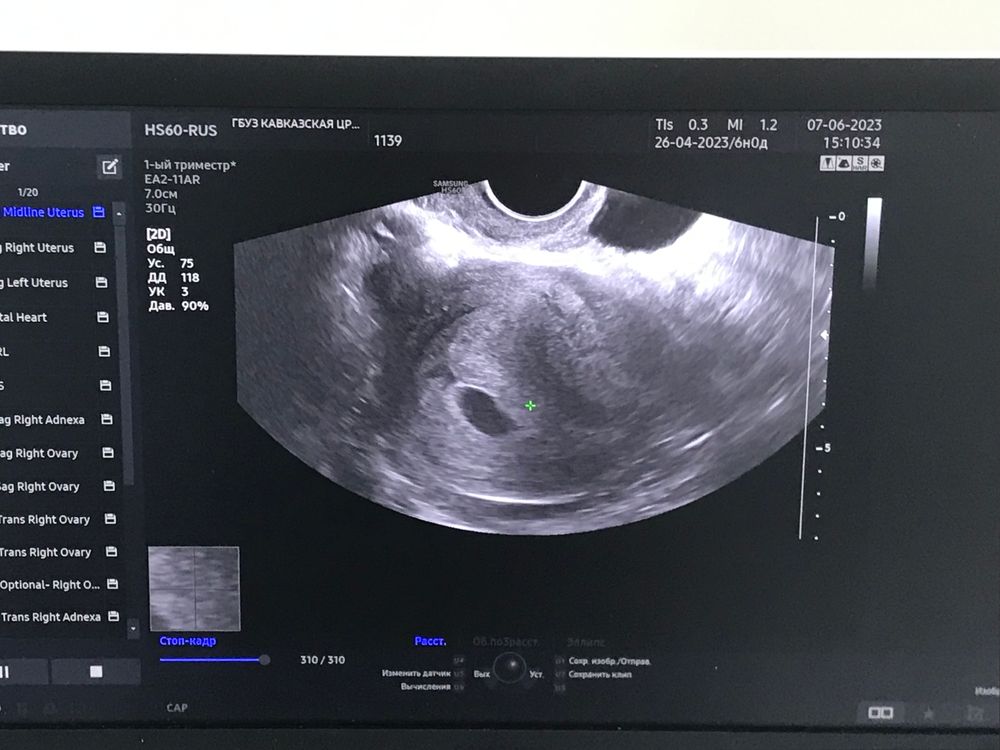

Сделала узи )

На 7 неделе уже желточный мешочек должен быть точно. А у вас его даже нет. Ну эмбрион с сердцебиением тоже находят. Может конечно очень поздняя овуляция...

Виктория, у меня 5 недель и 3 дня .

Эва , а на значке стояло 7 недель🤔Ну тогда рано конечно, ждите.

Фетальный доплер с 10 недель, я спокойна 🥰 Была на узи